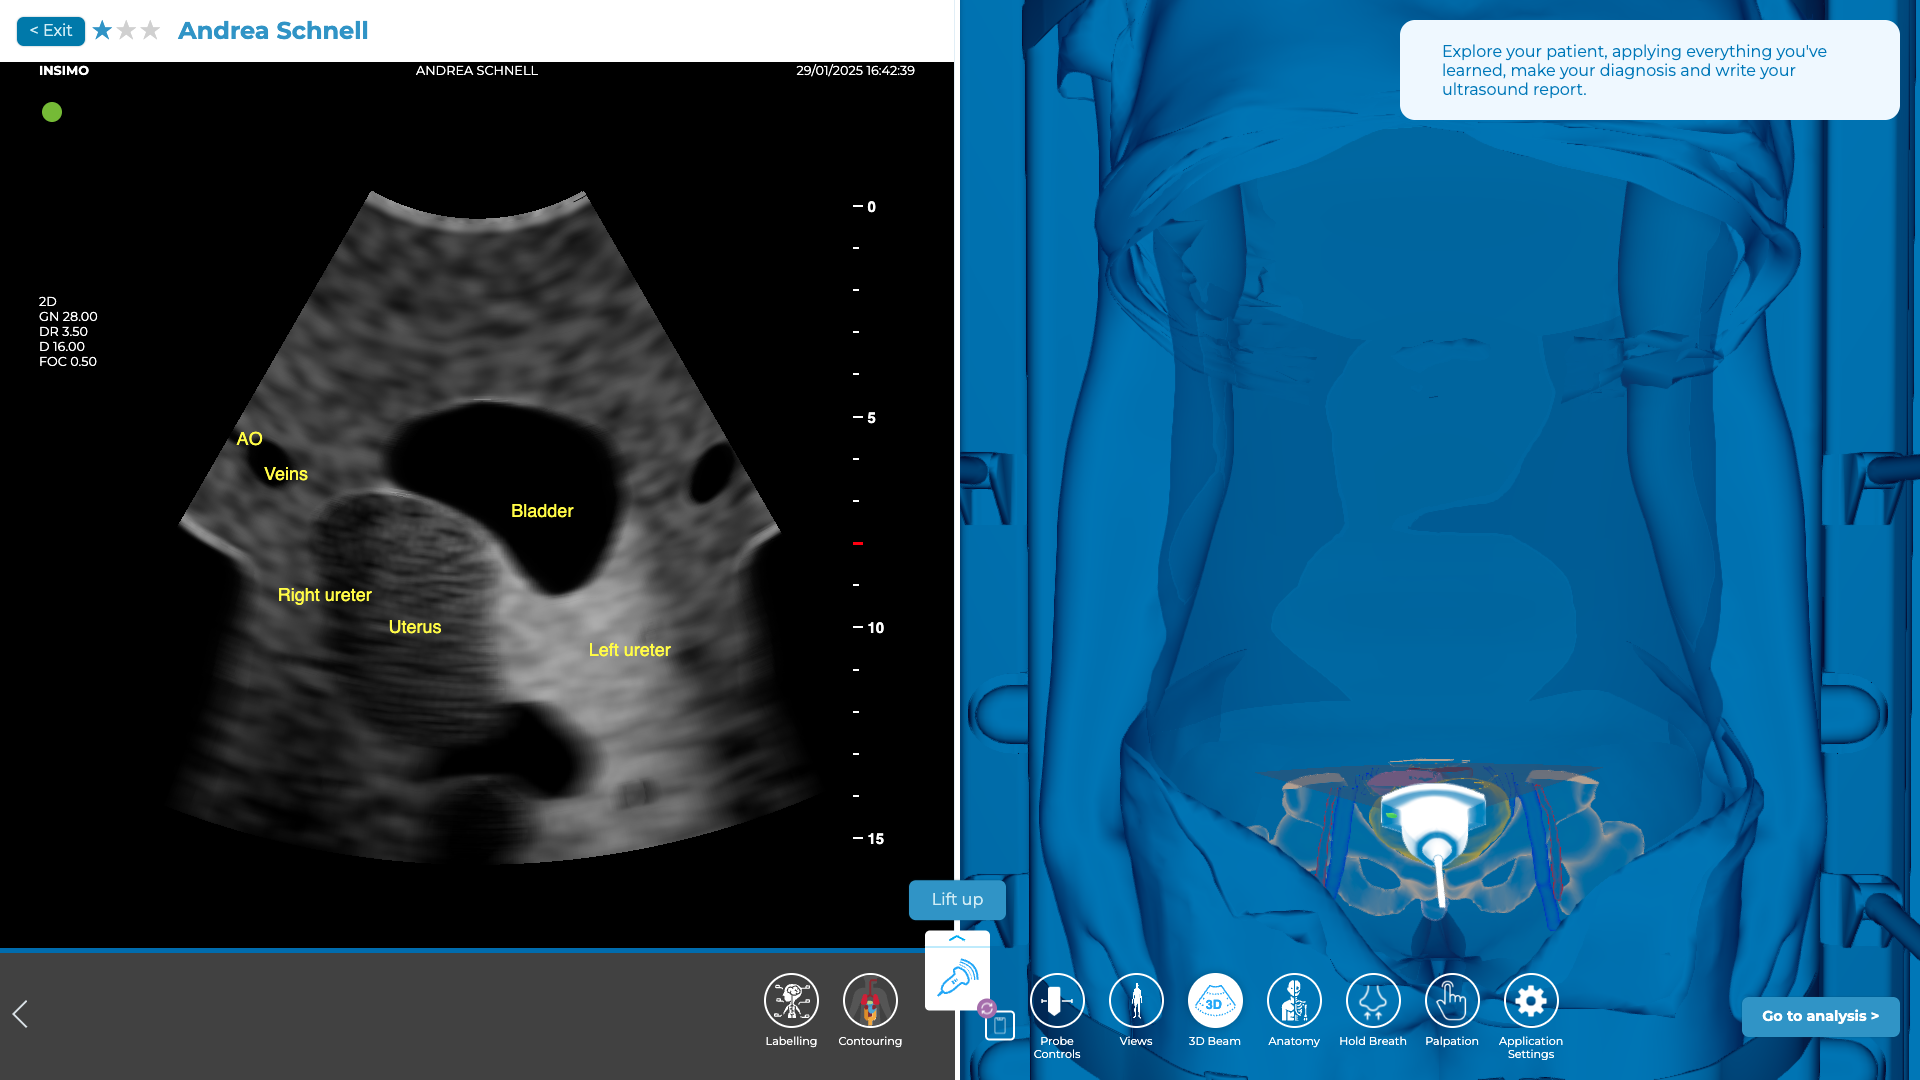

Evaluation de la région pelvienne (fenêtre sus-pubienne)

L’évaluation de la cavité pelvienne est essentielle pour détecter la présence de liquide libre, notamment dans le cul-de-sac de Douglas, chez la femme, ou dans la région recto-vésicale chez l’homme, ce qui peut indiquer un traumatisme abdominal bas ou une rupture d’organe, souvent en lien avec des blessures pelviennes, de l’utérus ou des ovaires chez la femme.

Pour explorer cette zone, commencez par localiser la symphyse pubienne et placez la sonde juste au-dessus, en la positionnant à l’horizontale pour examiner la cavité pelvienne. Il est important de tenir compte de l’état de la vessie du patient (vide ou pleine), car cela peut modifier la visibilité de la région pelvienne et vous demander d’ajuster la profondeur des paramètres échographiques. Si la vessie est pleine, cela peut gêner la visualisation du cul-de-sac de Douglas, mais si elle est vide, la vue sera plus claire, notamment pour observer les épanchements dans la région pelvienne. Balayez ensuite caudalement et céphaliquement pour obtenir une vue complète de la zone.

Chez la femme, l’espace à examiner est la poche recto-utérine, qui se situe derrière l’utérus et devant le rectum. C’est ici que le liquide libre s’accumule fréquemment en cas de traumatisme. Chez l’homme, la région à explorer est la zone recto-vésicale, qui se situe entre le rectum et la vessie [12].

Exploration de la région pelvienne sur diSplay U/S